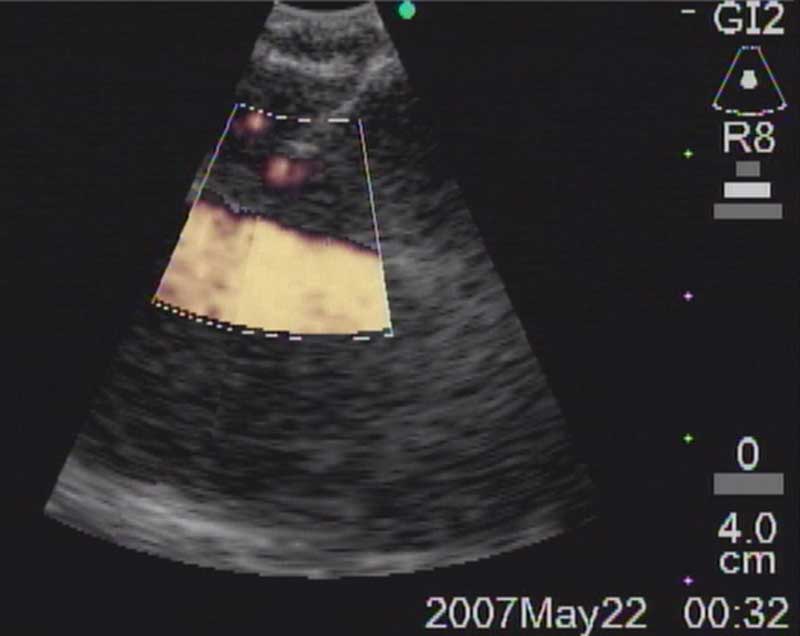

The easiest place to start ultrasound imaging is generally the right main bronchus and subcarinal areas. Pass the scope to the right side of the carina with the probe facing anteriorly and apply to the anterior wall of the RMB. This will bring into view the right main pulmonary artery. Vascular structures appear hypoechoic and pulsatile, and are usually readily discernable without using the color Doppler. If doubt persists flow within can be confirmed by switching to the Doppler overlay (B/CPD; Figures 5 and 6). Turn the scope 90 degrees counter-clockwise. This allows visualization of the subcarinal area from the right side. By moving the scope in and out the level 7 subcarinal node can usually be identified. If not, repeat this procedure in the LMB turning the scope 90 degrees clockwise instead. Once the subcarinal nodes are visualized it is relatively easy to identify other landmarks, by correlating anatomical location with the ultrasound image. It is useful to attempt to map out all nodes that you wish to biopsy first, before needle tract bleeding confounds the fiber optic image. The size of the node can be measured by freezing the US image [Freeze] and using the [Measure/Select] button and cursor scroll ball (Figures 5 and 7).

Figure 6a: Ultrasound image of R main pulmonary artery with (right) and without (left) color Doppler.